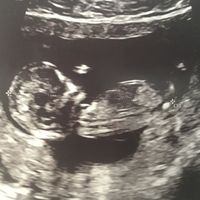

Ciao ragazze! Sono a 11+4 e stamattina ho fatto la T.N... sapreste dirmi se secondo la Nub Theory è maschio o femmina?? Alcune mi dicono femmina 😍 grazie 💕